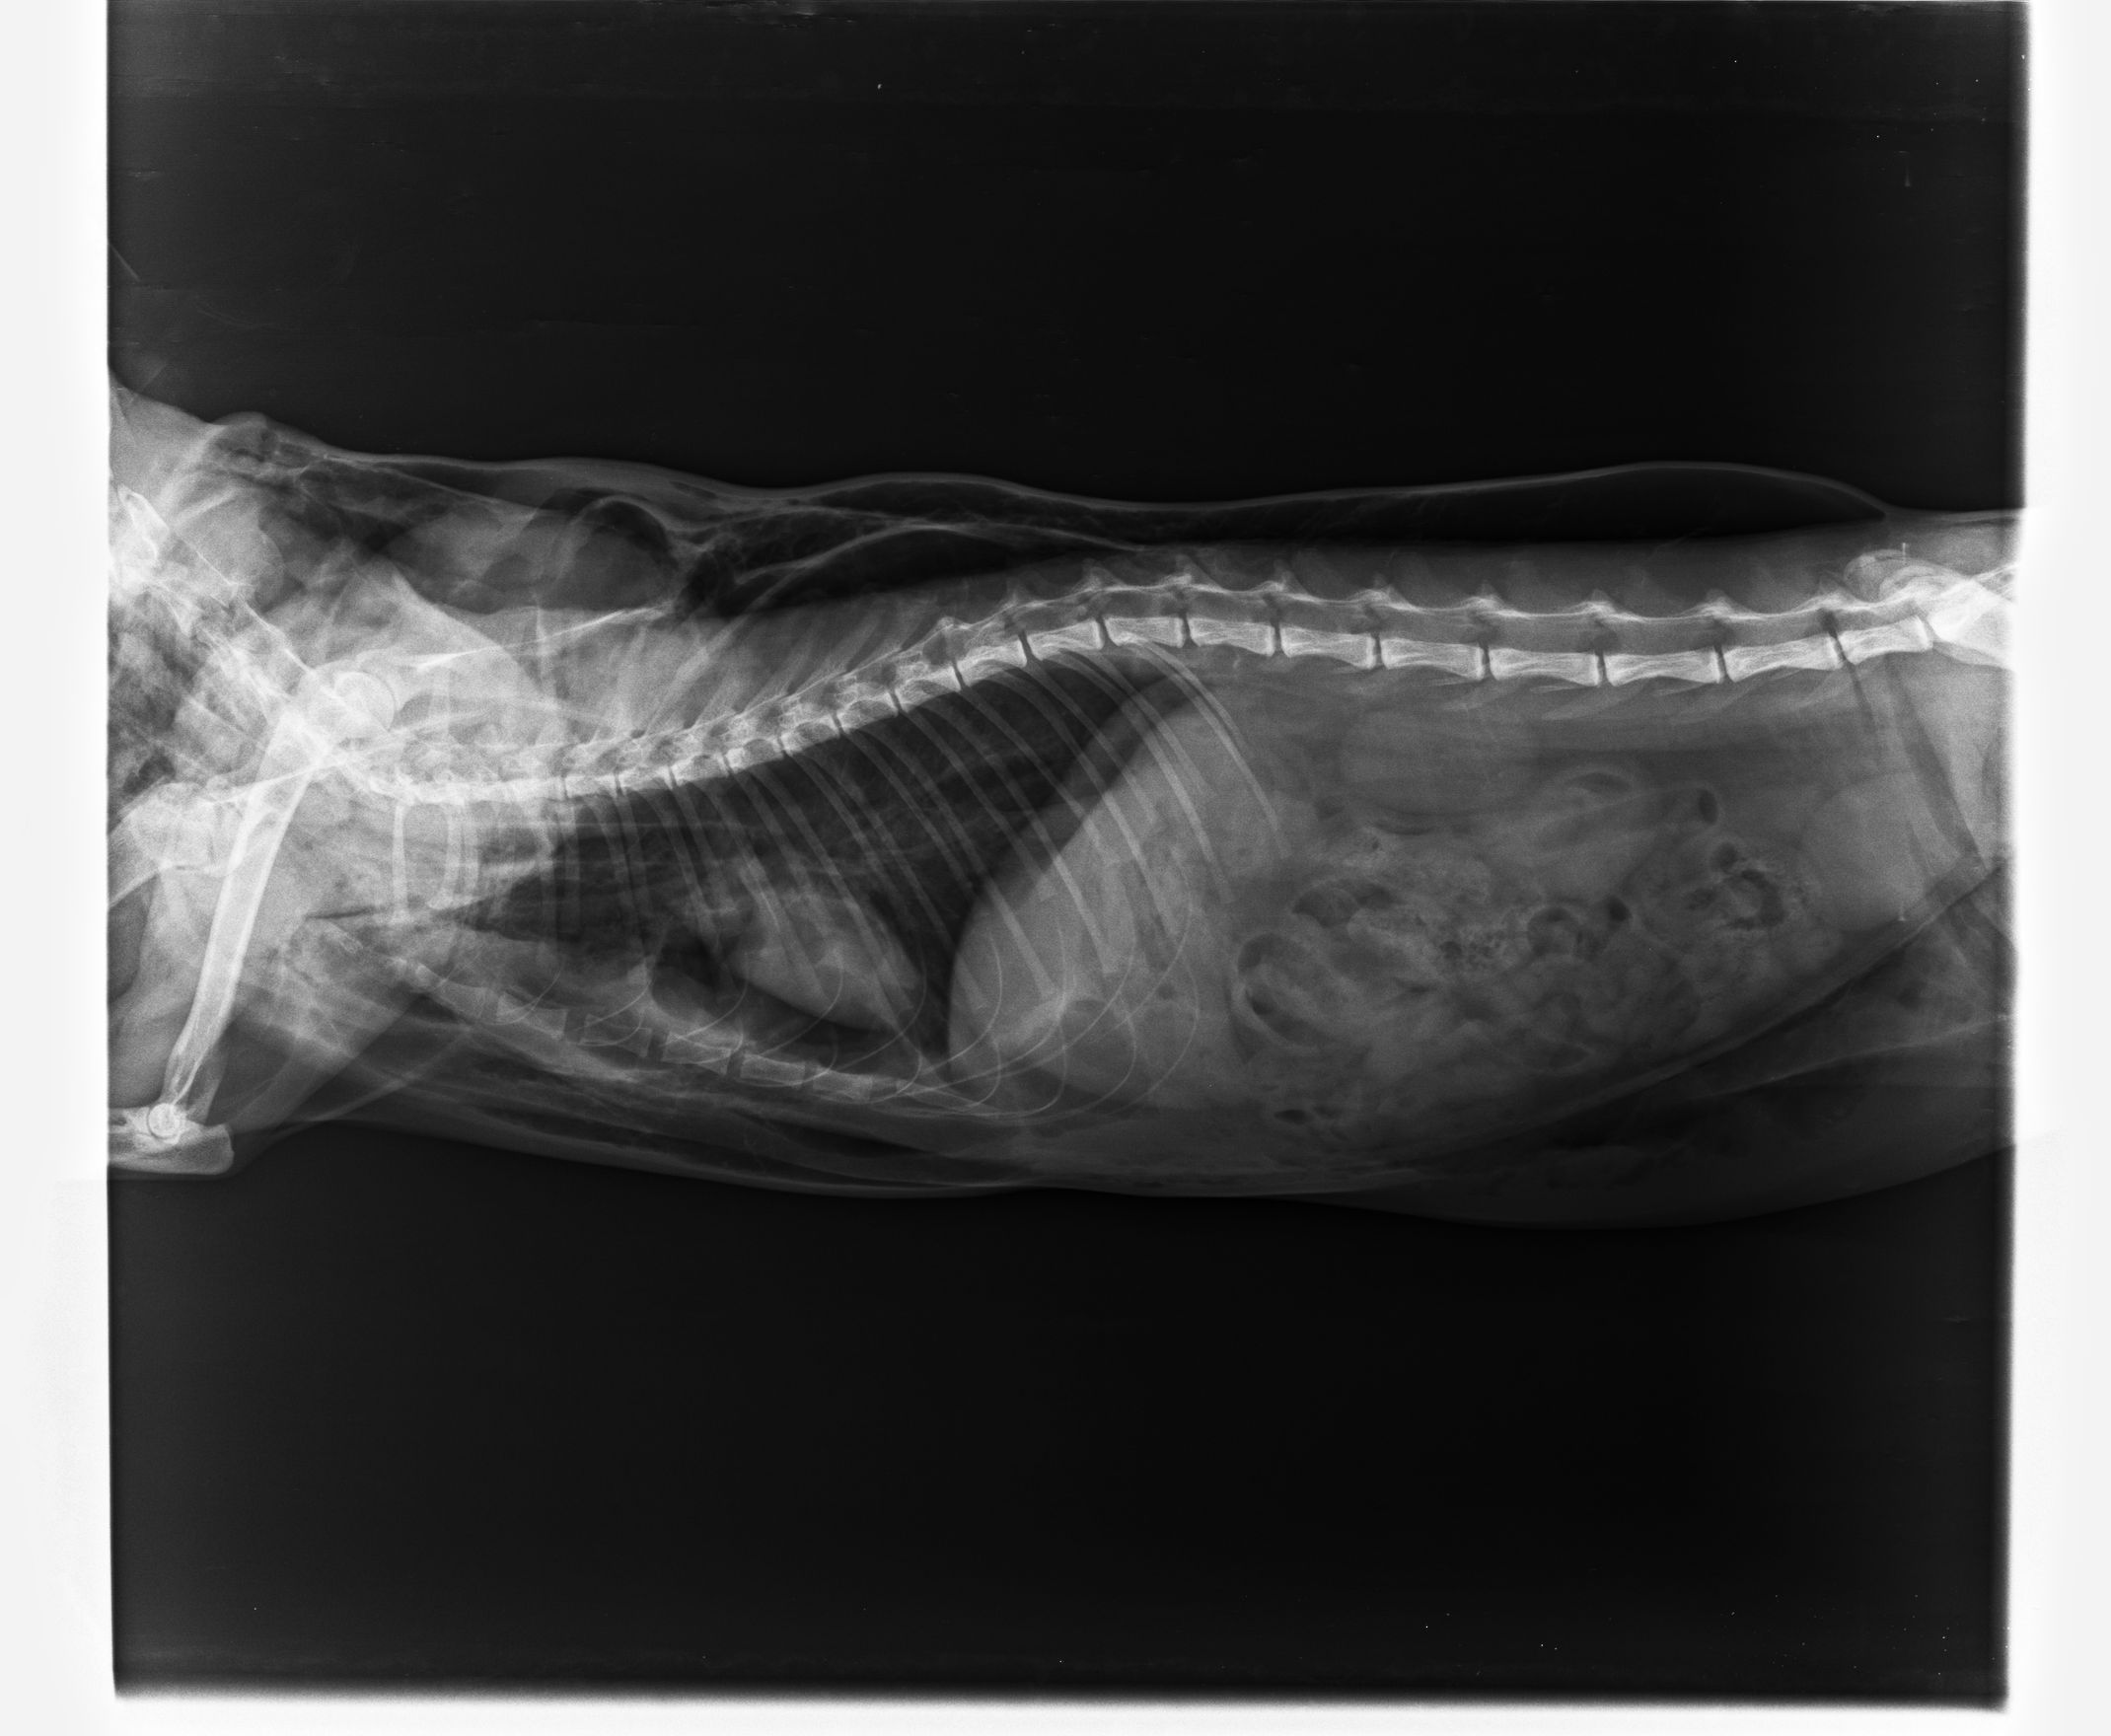

全身腫脹,醫生先判斷氣腫,X光片出來後確定氣腫嚴重,也有氣胸情況,皮膚和肉中間因充滿氣體造成分離,心臟也移位,醫生表示情況很差...先住氧氣房(太僕部分急救費用由志工自行負擔)